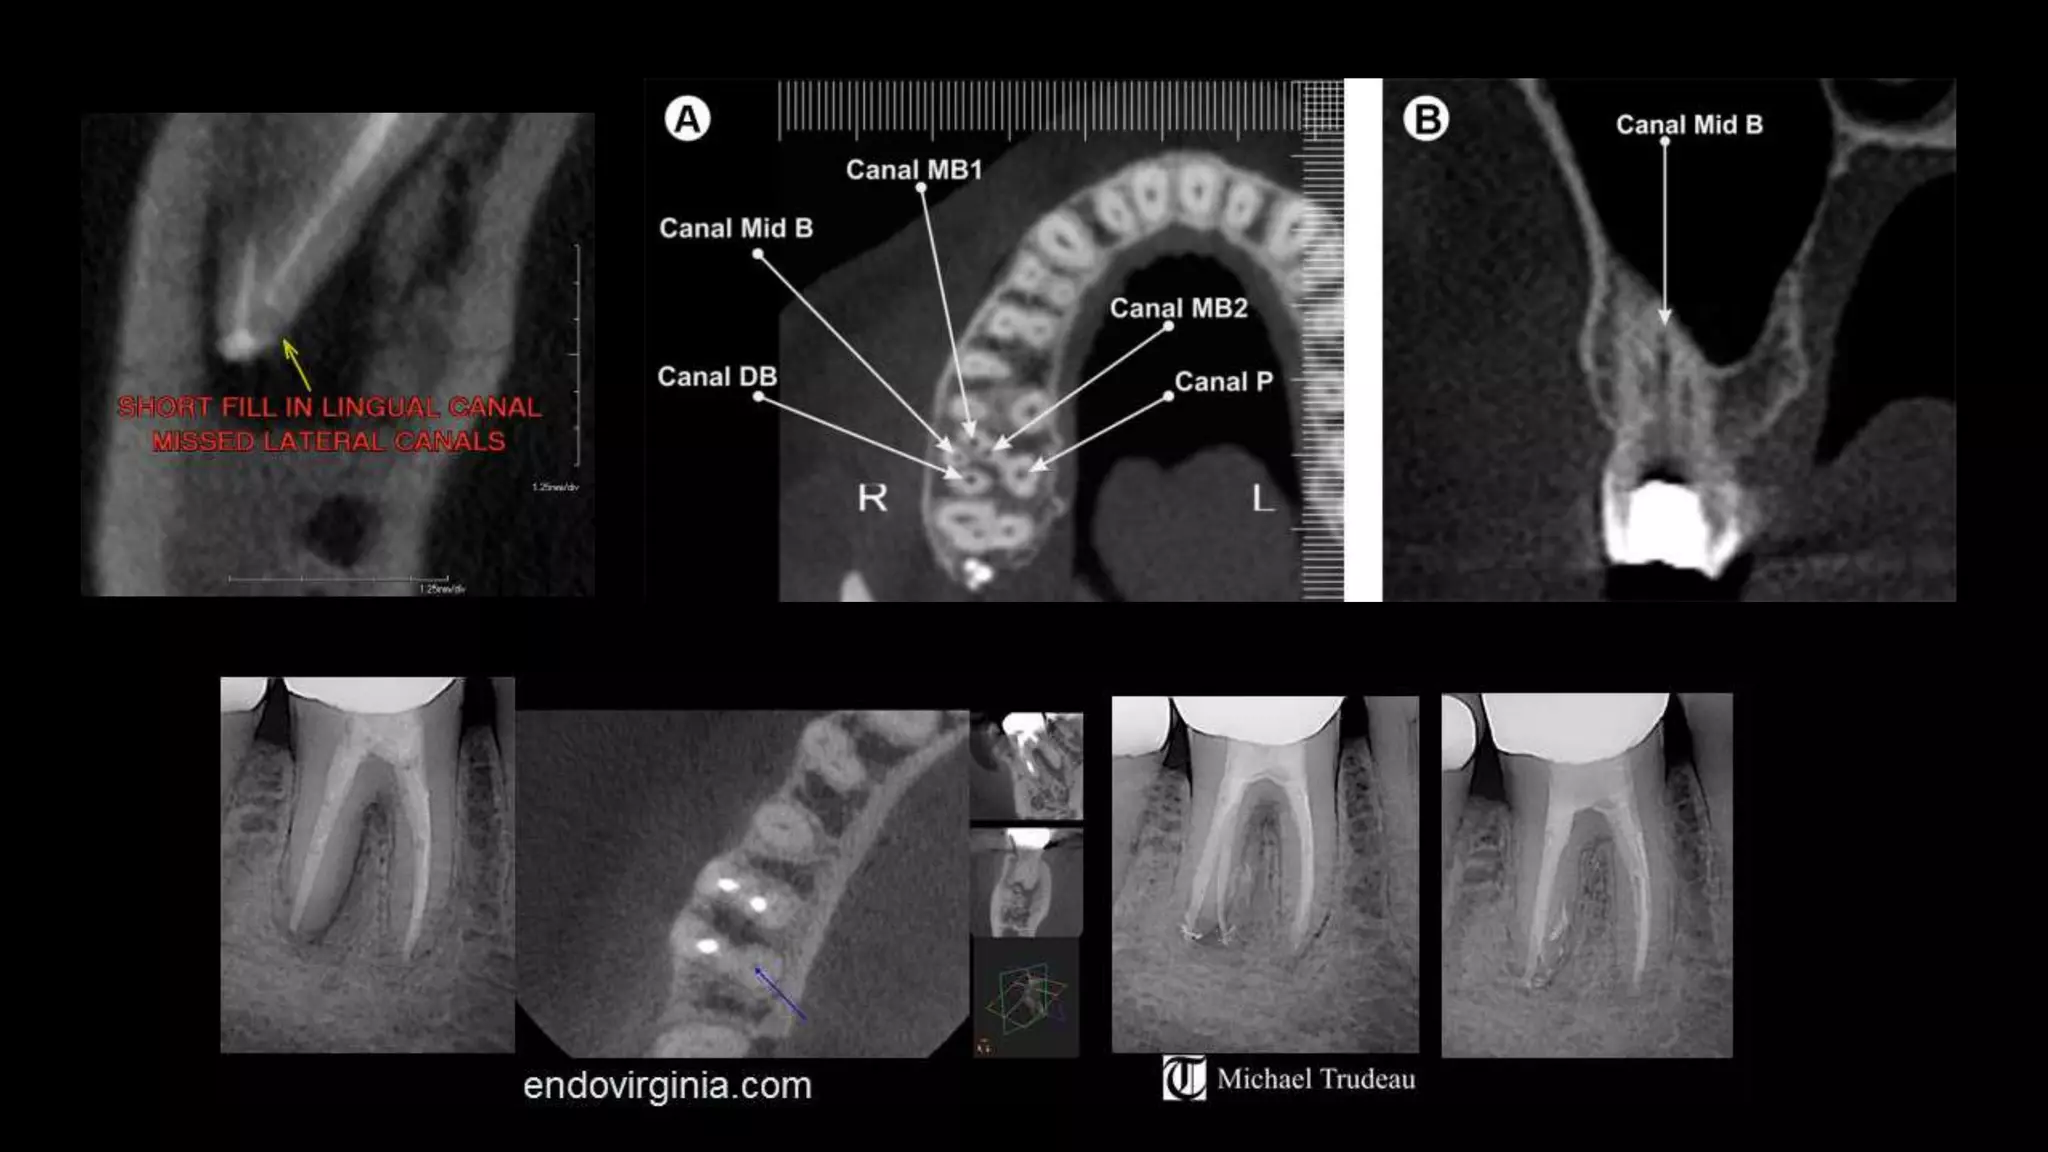

Concluded that maxillary first molar shows a very complicated canal

shape at the apical limit which makes cleaning & shaping followed by

obturation difficult, particularly in MB1 & distobuccal canals.

NI-TI

Controlled & directed canal preparation

into the bulky portions / safety zones,

away from the thinner portions of the

curved canals – which risk of stripping or

perforation – danger zone.

NI -TI

ISTHMUS

Schematic representation of isthmus classifications described by Kim et al.

Type I is an incomplete isthmus - faint communication between two canals.

Type II is characterized by two canals with a definite connection between them (complete isthmus).

Type III is a very short, complete isthmus between two canals.

Type IV is a complete or incomplete isthmus between three or more canals.

TypeV is marked by two or three canal openings without visible connections.